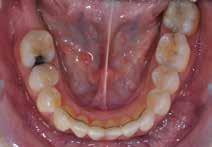

Vi viser her to ortodontiske behandlinger af patienter med velbehandlet stadie 3- og 4-parodontitis, som begge har tandtab og reduceret, men sundt parodontium, dog med begrundet undtagelse af en enkelt tand, som vi kommer tilbage til. Behandlingerne følger følgende princip:

PATIENTTILFÆLDE 1

Patienttilfælde 1 (Fig. 1) er en 37-årig kvinde, henvist efter succesfuld behandling af stadie 3-parodontitis. Der er nu sundt

Før behandling

parodontium, ingen pocher over 4 mm, og både blødnings- og plakindeks er under 10 %. Patienten er motiveret for ortodontisk behandling, da hendes tænder er vandret over tid, delvist som følge af reduceret parodontium.

Der ses anterior trangstilling i begge kæber og overerupterede 1+1 og 2,1-1,2, hvilket resulterer i dybt bid med 2- tæt på ganepåbidning. Der er normale sidetandsrelationer, men der ses 5 mm horisontalt overbid (HOB) og 7 mm vertikalt

overbid (VOB). Papillen mellem 1+1 er betydeligt reduceret pga. fæstetab, og de mesialt kippede 1+1 har resulteret i en ”dark triangle”. Den facioorale funktion er for nuværende i.a. Panoramarøntgen (Fig. 1, I) viser marginalt knogletab i begge kæber og fravær af 8,7+7,8 og 8,7-8.

Objektivt anbefales behandling af det dybe bid, som ubehandlet forventes at forværres yderligere over tid. Patienten har ønske om behandling med æstetisk ortodontisk apparatur, alignere, og det vurderes muligt at behandle malokklusionen med alignere. Dog anbefales det generelt, at alignere undgås eller benyttes med væsentlige modifikationer af alignerens retention ved tandmobilitet, da dette ellers kan medføre jiggling, når aligneren tages af og på mange gange dagligt. På den anden side er der nogen evidens for, at alignerbehandling er associeret med bedre renhold og parodontal sundhed sammenlignet med fast apparatur (16).

Der planlægges alignerbehandling af begge kæber med intrusion af 1+1 og 2,1-1,2, nivellering af trangstilling UK med interproksimal reduktion (IPR) (Fig. 2 A, B) og senere IPR OK for reduktion af dark triangles mellem incisiverne efter nivellering. Patienten instrueres i at benytte alignere 20-22 timer/ dag med alignerskift hver 7. dag, og patienten ses hver 3.-8. uge under forløbet. Den første alignerserie består af 16 alignere for nivellering OK/UK og IPR i UK (Fig. 2). Efter denne serie planlægges IPR mellem incisiverne i OK for reduktion af dark triangles (Fig. 3) samt yderligere intrusion af OK og UK-fronten i 12 refinement-alignere. Patienten udviser god kooperation og er meget tilfreds med alignerapparaturet, som er mindre synligt end det faste apparatur (Fig. 4).

Behandlingen afsluttes med yderligere refinement-alignere for finindstilling af okklusionen, og efter 11 måneders ortodontisk behandling er der opnået normale relationer i alle tre